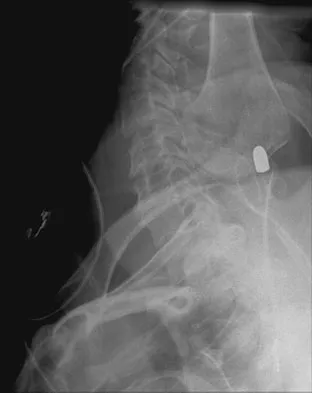

A 61-year-old man reports right hip pain and limited motion after undergoing total hip arthroplasty for posttraumatic arthritis 1 year ago. Figure 6 shows an AP radiograph of the pelvis. To improve motion and relieve pain, management should consist of

Explanation

The patient has symptomatic grade IV Brooker heterotopic ossification. Once the bone has matured, it can be excised. Surgical excision should be combined with postoperative irradiation to avoid recurrence. Pharmacologic and irradiation intervention are not successful beyond the perioperative period unless they are combined with surgical excision of mature heterotopic ossification. Koval KJ (ed): Orthopaedic Knowledge Update 7. Rosemont, IL, American Academy of Orthopaedic Surgeons, 2002, pp 417-451.